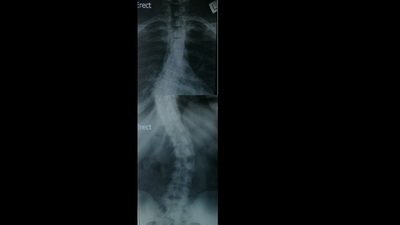

My name is Leilah, I am 22 and I suffer from scoliosis. Scoliosis is an abnormal curvature of the spine, and has various degrees of severity. It’s a condition that affects approximately 4% of the population, or 1 in every 25 people. Some people can lead normal lives with scoliosis, but others require alternative treatments like bracing, monitoring and in severe cases - surgery (spinal fusion).